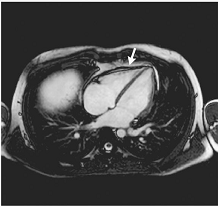

Наиболее часто в онкологической практике МРТ

необходима для дифференциальной диагностики первичных и вторичных опухолей

центральной нервной системы (ствол и спинной мозг), сердца и перикарда,

позвоночника.

МРТ центральной нервной системы

МРТ сердца МРТ желудка и кишечника